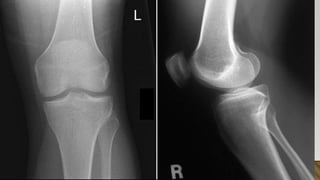

This document discusses radiology and the use of x-rays. It begins with an introduction to radiology and x-rays, noting their importance as the "father of medical investigations." It then discusses anatomy as seen on radiographs and whether x-rays are enough. The document goes on to compare gross views to radiological views, noting what each can and cannot show. It highlights important figures in the development of radiology, from x-rays to CT, MRI, and ultrasound. Specific anatomical structures visible on upper and lower limb x-rays are listed. The document concludes by discussing how pathologies appear on x-rays and the importance of clinical history and knowledge when interpreting radiological images.